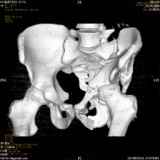

Уважаемые коллеги! Хотелось бы услышать совет по тактике лечения представлленого больного.Поступил после лечения в одном изотделений области. Травма 2,5 месяца назад. После выведенияиз шока был произведен остеосинтез перелома бедра, предплечья, до перевода к нам проводилосьвытяжение по оси шейки бедра за стержень, введенный в большой вертел. На сегодня деформацияригидна, клинически мобильности не определяется. Заранее признателен. P.S. Данный вид травм не включен в перечень "высокотехнологичных операций", направить длялечения по квотам Минздрава очень сложно.

Тяжелый случай... Поздняя реконструкция такого перелома технически сложное дело, вероятность осложнений,неуд.результатов выше(на PubMed article Johnson, Mast, Matta, Letournell results of acetabular reconstruction 20-120 days after injury).

Принимая во внимание обширность реконструкции, вероятность осложнений( остеоартроз, аваскулярный некроз), которые в любом случае должны будут решаться артропластикой сустава, пожалуй, я бы не стал оперировать сейчас: складывать мозаику многооскольчатого перелома, мобилизуя фактически сросшиеяся воедино фрагменты - дело травматичное с сомнительным результатом.

Думаю, что стоит подождать полной консолидации переломов и месяца через 3-4 при условии неудовлетворительной функции сустава артропластика.

Привет, Леонид. Оскольчатый высокий двухколонный перелом в такие сроки трогать не надо, т.к. это про такие переломы сказано: "кто с ножом на Ж. пойдет тот в ней и останется...".

Может быть неплохой результат при консервативном лечении и ранних движениях.

Если заболит после начала нагрузки в 4-6 месяцев - эндопротез.

Спасибо за отклики. Мы решили также пока занять выжидательную тактику, позднее решать вопрос об

артропластике.